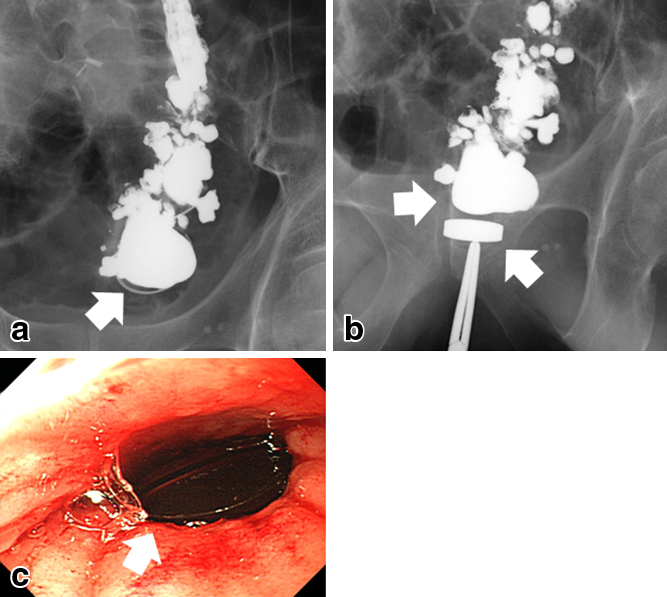

Yamanouchi method (coronal contrast/colonoscope). a) A disc-shaped magnet was inserted under colonoscopic guidance from the stoma side. The white arrow shows the guide wire. b) The other disc-shaped magnet was inserted from the anal side (diameter 17.5 mm, thickness 5 mm). The two magnets sandwiched the occlusion area. Intestinal tract. c) We confirmed that the magnet was adsorbed by the colonoscope from the anus.

経過:内視鏡下に肛門と人工肛門の両側からそれぞれ直径17.5 mm,厚さ5 mmのサマリウムコバルト系希土類磁石を挿入し,両磁石で閉塞部組織を挟み込む形で圧迫した.磁石側面には穴が開いており,この穴に内視鏡の先端から出したガイドワイヤーを通した状態で,人工肛門から閉塞部へ先端を進めていく.磁石がガイドワイヤーから抜け落ちないように注意し,閉塞部に達してからガイドワイヤーを抜き,内視鏡の先端で閉塞部の底面に磁石が平行となるように調節する.肛門側の磁石はペアンで押し込み,透視下で位置を決定した4)(Fig. 3).

施術後5日目では圧迫磁石にずれはなく(Fig. 4a, b),8日目に肛門から圧迫磁石の脱落があり,閉塞部組織は両磁石に圧迫壊死した形で排出され,使用した磁石と同直径の開通を得た(Fig. 4c, d).再狭窄を防ぐために,再開通部が安定するまでは,外来で2週間毎に3か月間,硬性ブジーによる拡張を行った.二つの磁石に圧着されて脱落した閉塞部組織は,直腸の線維組織として矛盾なく,悪性所見はなかった(Fig. 5).

Study after the Yamanouchi method. a, b) On day 5, two magnets sandwiched the occlusion area (arrows). c, d) On day 8, both magnets were removed and eliminated. The diameter of recanalization was the same as the magnets (arrows).